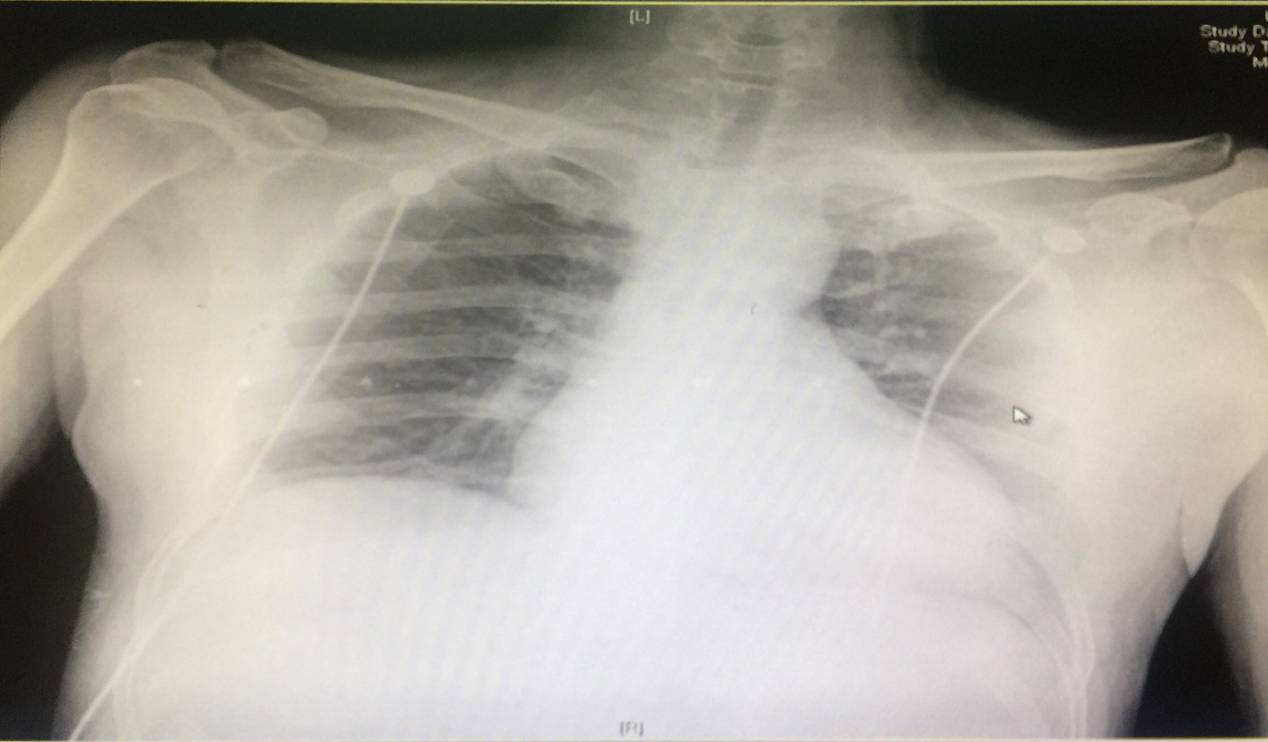

胸片

一、X线检查 心影普遍增大,合并心力衰竭时可有肺淤血、肺水肿甚至胸腔积液。

◆胸片示: 两肺轻淤血,左室增大。